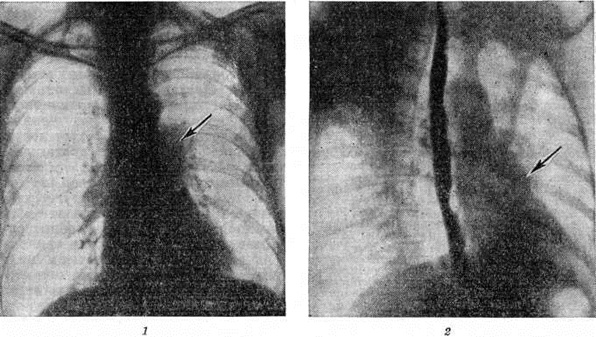

Рентгенодиагностика. Рентгенологические картина при Лёгочное сердце вариабельна и зависит от стадии и характера лёгочного заболевания. В начальных стадиях развития Лёгочное сердце у больных с выраженной эмфиземой лёгких при рентгеноскопии и рентгенографии в прямой и косых проекциях отмечаются относительно небольшие размеры сердца. Возможны признаки гипертрофии путей оттока от правого желудочка: выбухание лёгочного конуса в прямой и правой косой проекциях (рисунок 4), в выраженных случаях выступающая по левому контуру вторая дуга лёгочного конуса может имитировать «митральную» конфигурацию сердца.

Расширение лёгочного ствола и лёгочных артерий часто сочетается с сужением более мелких их разветвлений (симптом «ампутации» корня) и обеднением периферического сосудистого рисунка лёгких (рисунок 4). Это особенно отчётливо обнаруживается на томограммах и зонограммах лёгких.

В последующих стадиях развития Лёгочное сердце рентгенологически определяется прогрессирующее увеличение правого желудочка за счёт гипертрофии, а затем и дилатации. При значительном расширении правого желудочка он может оттеснять левый желудочек кзади и становиться краеобразующим как по правому, так и по левому контуру сердца. В стадии декомпенсации сердце расширяется вправо главным образом за счёт расширения правого предсердия.